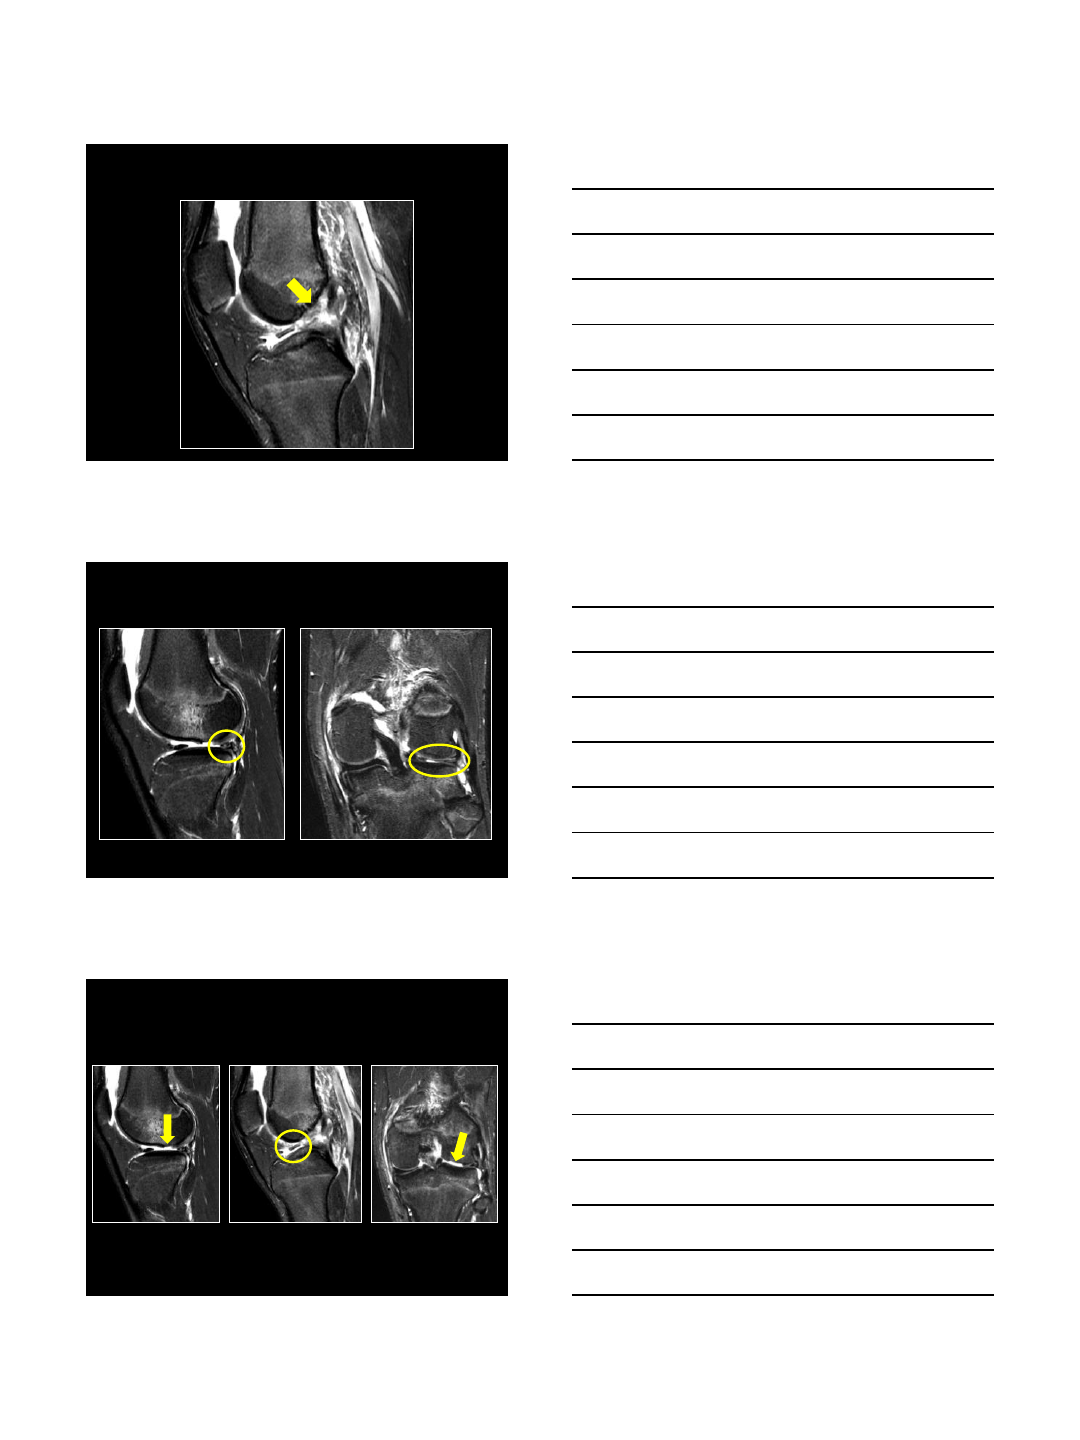

MRI –ACL Tear

MRI –Lateral Meniscus Tear

MRI –Chondral Defect/Loose Body

ACL: Complete Tear

Primary signs

•edematous mass

• “empty notch”

•irregular, horiz contour

•focal disruption

Diagnosis

•Left knee ACL tear

•Left knee complex bucket-handle lateral meniscus tear

•Left knee lateral femoral condyle chondral fracture

with loose body